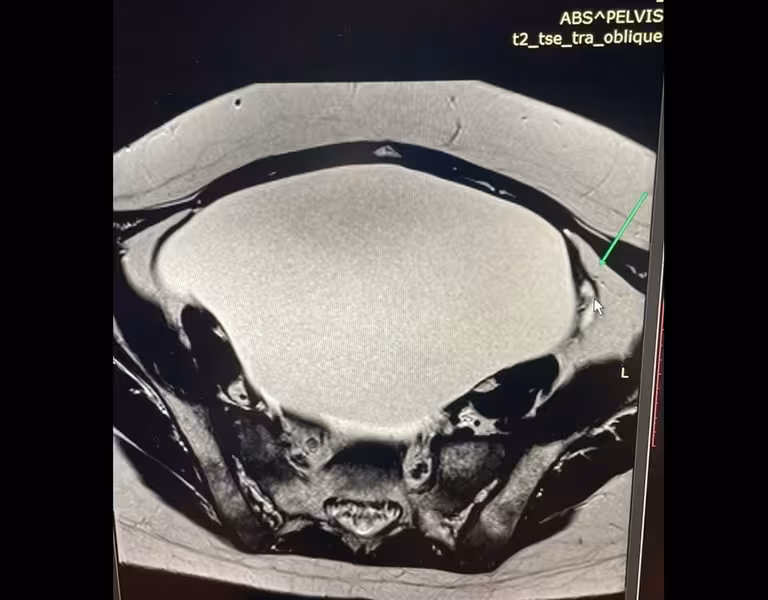

Львівські лікарі видалили дівчинці гігантську пухлину (ФОТО)

Львівські лікарі видалили із яєчників 14-річної дівчини 3-кілограмову пухлину. У пацієнтки був збільшений живіт, який їй заважав. Про це «Варта1» розповіли у Львівському охматдиті.

«Дівчинка з 9 років хворіє на лейкемію. Вона отримувала все необхідне лікування — і променеву, і хіміотерапію. В Італії їй зробили пересадку кісткового мозку. Зараз вона у ремісії. У процесі лікування пацієнтка мала також гормональну терапію, ймовірно, це і стимулювало ріст пухлини у яєчнику. Батьки дівчинки зверталися в різні клініки до різних спеціалістів вже з новою проблемою, їм рекомендували стежити за «кістою», проте в якийсь момент утворення досягло просто гігантських розмірів», — розповідають у лікарні.